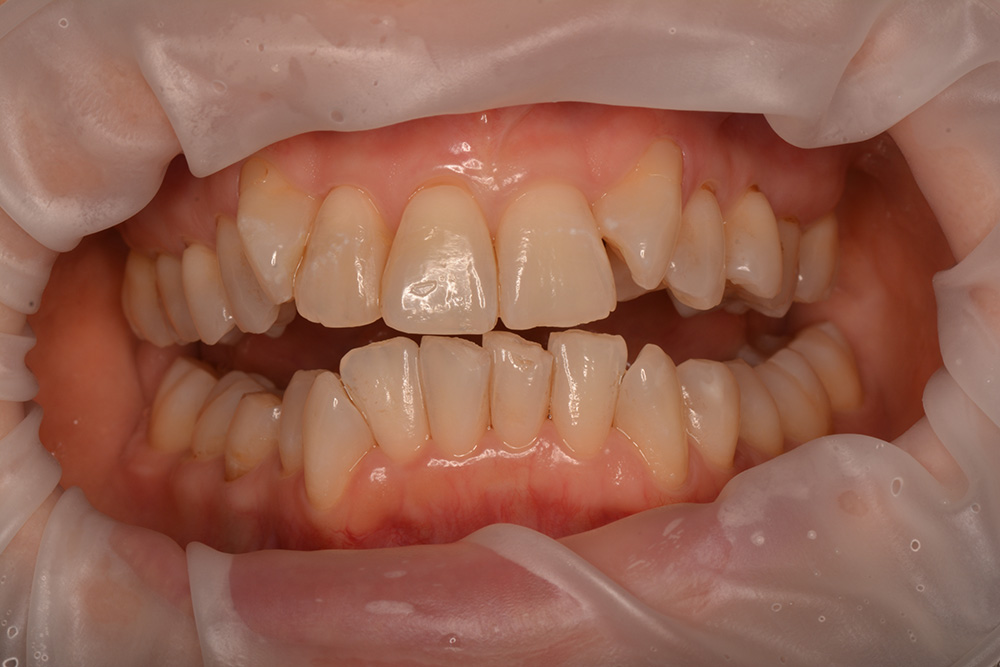

術前

術後

世代・性別

10歳女性

主訴

前歯が出ているのを治したい

治療内容

筋機能矯正治療(治療途中)

治療期間

4ヶ月

治療費

27万円(税別)

治療のリスク

歯の移動に伴う痛み